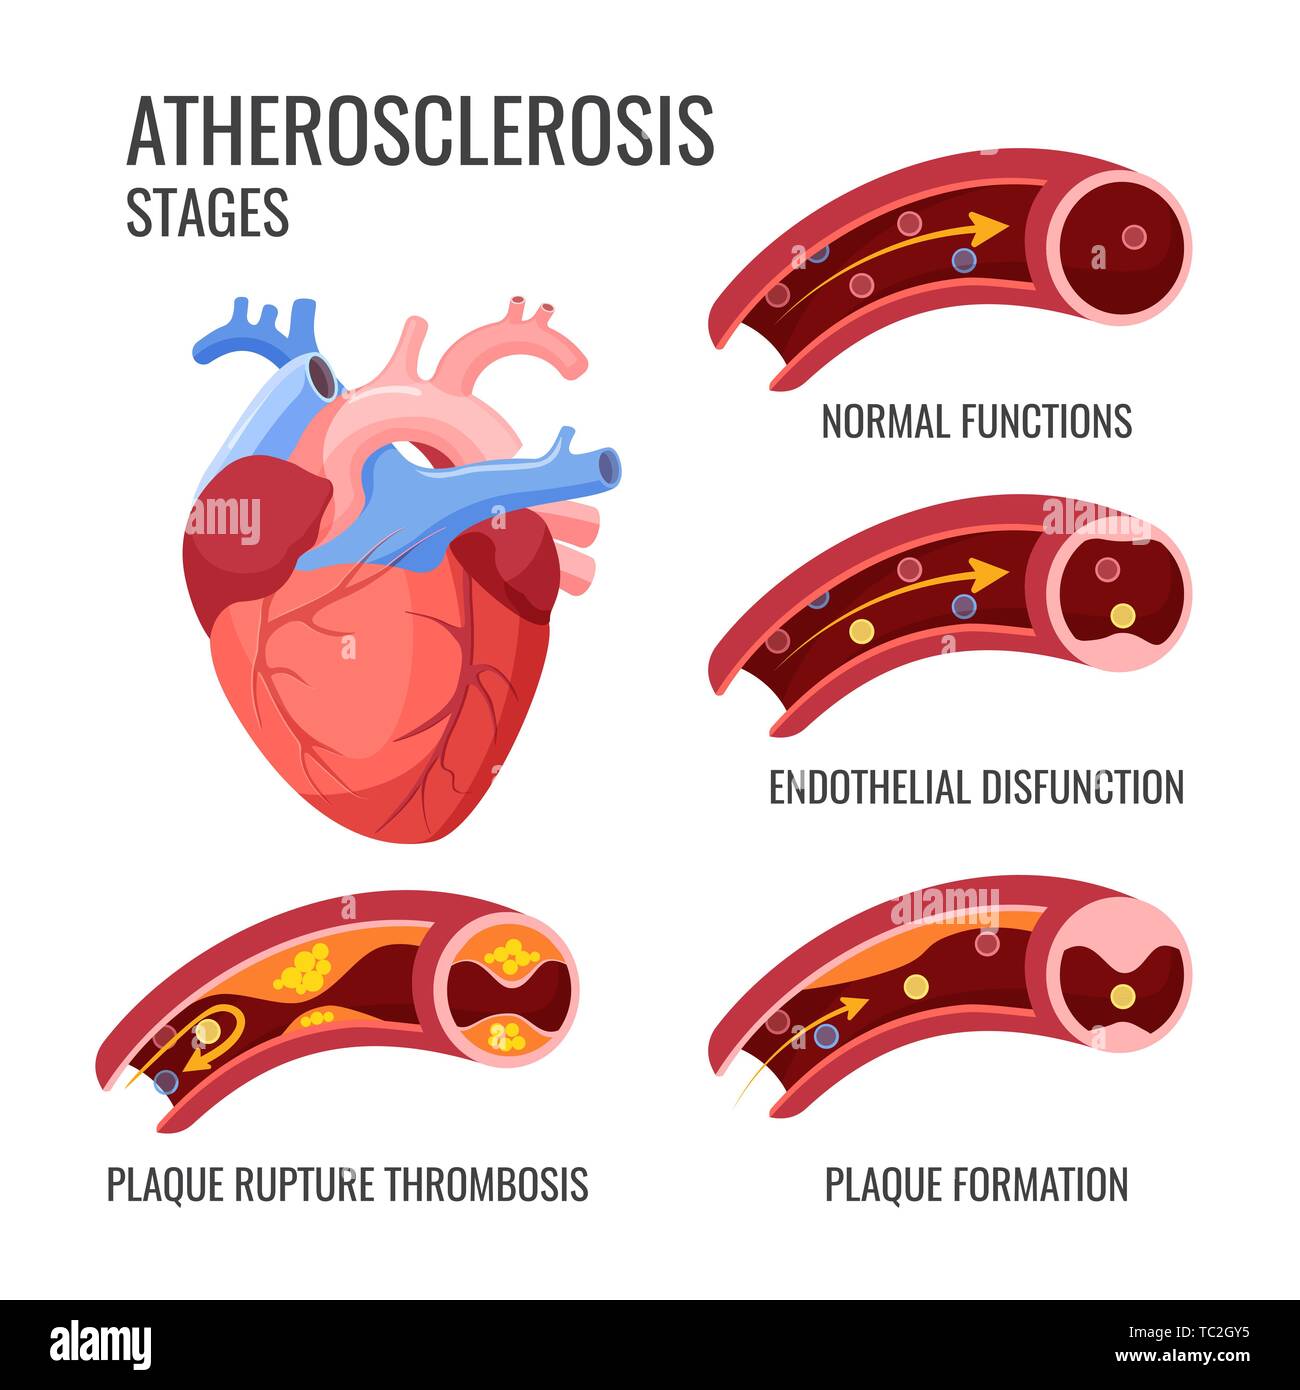

Atherosclerosis stages. Normal functions, endothelia disfunction, plaque formation, plaque rupture thrombosis. Arteriosclerotic vascular disease or AS Stock Vectorhttps://www.alamy.com/image-license-details/?v=1https://www.alamy.com/atherosclerosis-stages-normal-functions-endothelia-disfunction-plaque-formation-plaque-rupture-thrombosis-arteriosclerotic-vascular-disease-or-as-image248378233.html

Atherosclerosis stages. Normal functions, endothelia disfunction, plaque formation, plaque rupture thrombosis. Arteriosclerotic vascular disease or AS Stock Vectorhttps://www.alamy.com/image-license-details/?v=1https://www.alamy.com/atherosclerosis-stages-normal-functions-endothelia-disfunction-plaque-formation-plaque-rupture-thrombosis-arteriosclerotic-vascular-disease-or-as-image248378233.htmlRFTC2GY5–Atherosclerosis stages. Normal functions, endothelia disfunction, plaque formation, plaque rupture thrombosis. Arteriosclerotic vascular disease or AS